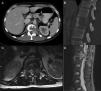

Presentamos el caso clínico de un paciente con dolor lumbar crónico irradiado a muslo izquierdo, diagnosticado por neuroimagen de lesión lítica en cuerpo vertebral de L1. Se realizó biopsia transpedicular que confirmó el diagnóstico de tumor de células gigantes. Fue intervenido quirúrgicamente mediante vertebrectomía L1 e implantación de cilindro de titanio sustitutivo por vía anterior y, a continuación, extirpación de arco posterior de L1 e implante de tornillos pediculares por vía posterior.

We report the case of a 32-year-old patient complaining of chronic low back pain radiating to his left thigh. His MRI showed a lytic L1 vertebral body injury. A transpedicular biopsy confirmed the diagnosis of giant cell tumor. He underwent a L1 vertebrectomy and vertebral body replacement with a titanium cylinder using anterior approach, followed by the removal of the L1 posterior arch and the placement of pedicle screws through a posterior approach.